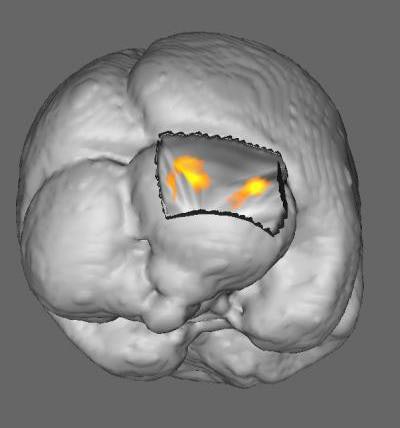

The group looked at fMRI scans of 22 girls to analyze the relationship between engagement and verbal interactivity while a mother reads to her child. The children who showed greater interest in the reading interaction showed increased activation in right-sided cerebellar areas of the brain, which are associated with cognitive skills connected to language and executive function.

Evidence shows the benefits of shared reading may improve literacy and brain development. Image courtesy of Cincinnati Children's.

Evidence shows the benefits of shared reading may improve literacy and brain development. Image courtesy of Cincinnati Children's."The takeaway for parents in this study is that they should engage more when reading with their child, ask questions, have them turn the page, and interact with each other," said lead author Dr. John Hutton, a pediatrician at Cincinnati Children's Hospital, in a statement.